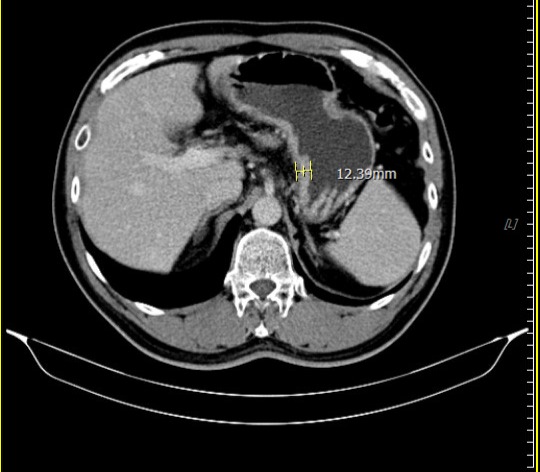

在為期兩個月的術前免疫治療合併化療期間,病人雖出現噁心、掉髮、倦怠等副作用,但家人每日陪伴、鼓勵,使他能堅定完成療程。隨著治療進展,患者症狀逐漸改善,胃痛減緩、進食量增加、精神與體力明顯好轉,全家人的心情也從陰霾中逐步走出。 腹部斷層掃描(治療後)

腹部斷層掃描(治療後)

經義大醫療外科團隊進一步評估後,患者體況已達手術標準,並順利接受胃部腫瘤切除手術。手術後的病理報告更帶來令人振奮的結果:腫瘤組織中未發現殘存癌細胞,成功達成「病理完全反應」。得知結果的當下,患者與家屬喜極而泣,醫療團隊也深感欣慰,這不僅是治療上的成功,更是病人、家屬與醫療團隊共同努力的成果。